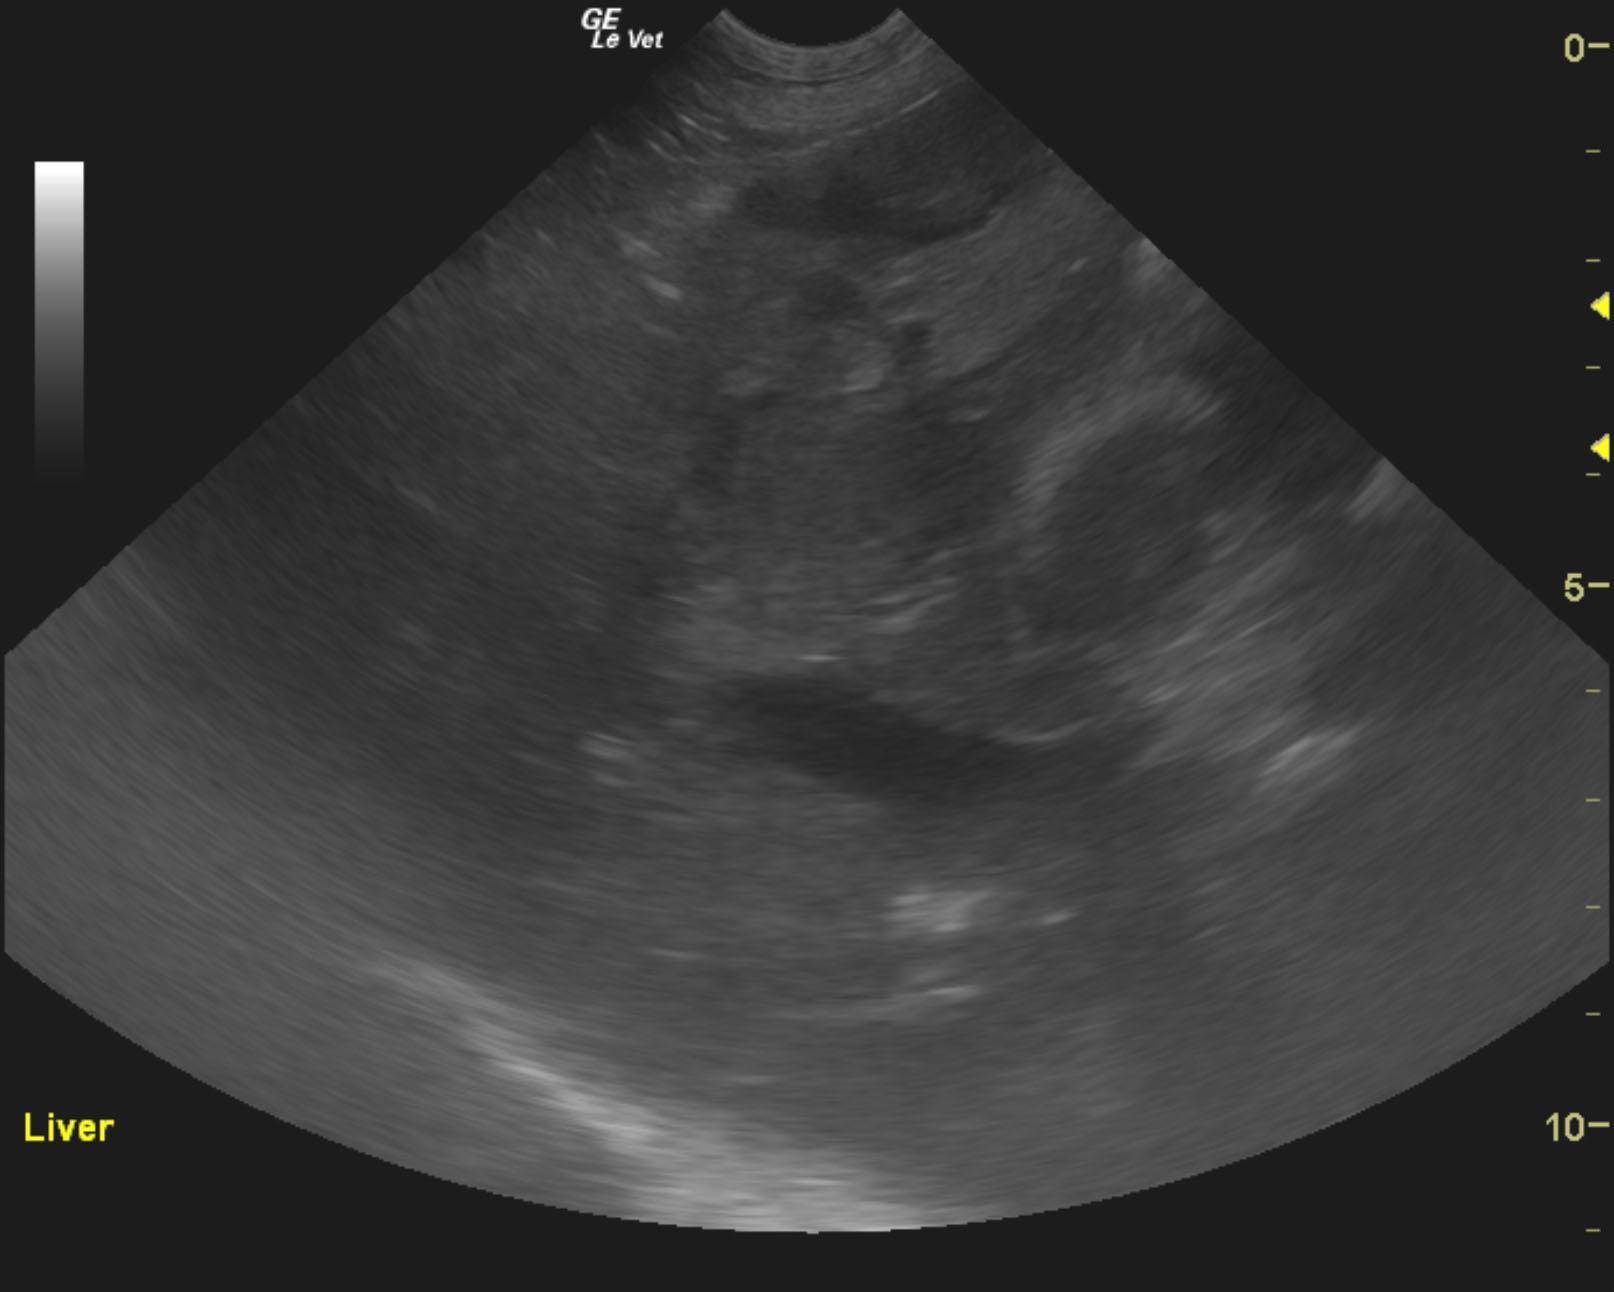

The pancreas revealed an extensive 9.7 x 7.5 cm, mixed, hypoechoic mass. The liver and spleen were riddled with multiple hypoechoic expansive nodular masses. Free fluid was noted adjacent to the spleen, which is mildly swollen. The gallbladder was unremarkable. There was also regional lymphadenopathy, with enlarged hepatic, iliac and aortic lymph nodes. Regional inflammation was noted throughout the cranial abdomen.

FNA of the liver and pancreas were consistent with malignant spindle cell tumor.